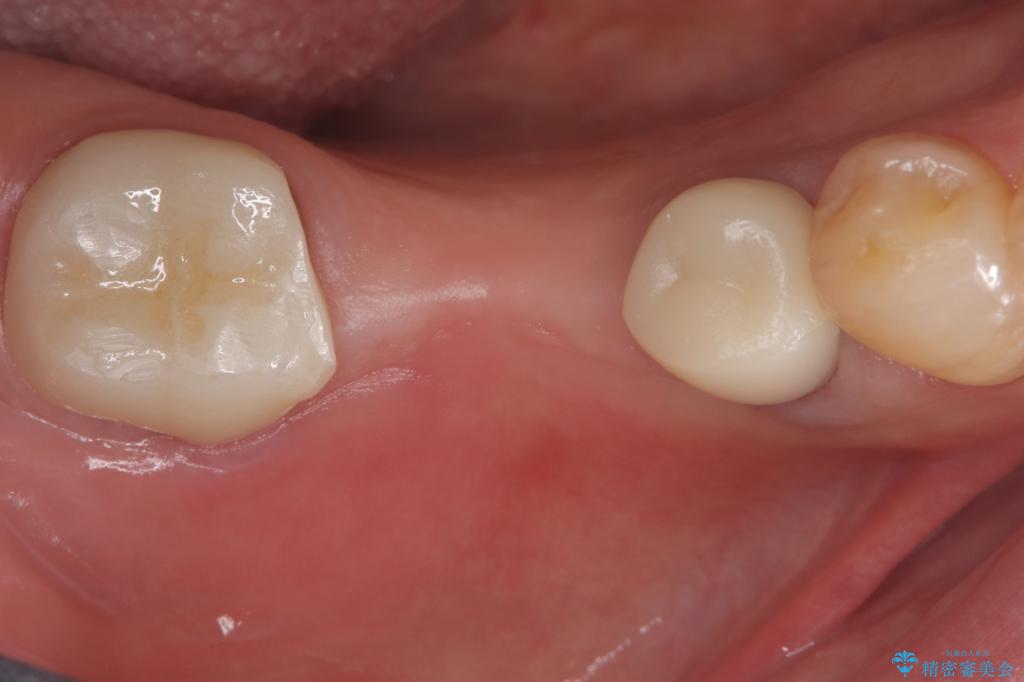

セラミックに比べ、破折リスクの少ない金属を使用したブリッジでのやり替えとなりました。

両支台歯が失活歯のため、どちらかもしくは両方の歯が破折した際、再度ブリッジを除去した治療が必要になるリスクとインプラント治療のご提案もさせていただきましたが、ブリッジでの治療を希望されました。

右下5番は支台歯CR築造を行っています。